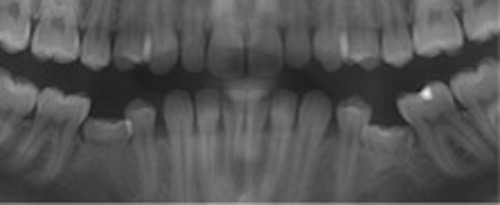

Infraocklusion av tänder innebär att tänderna befinner sig under ocklusalplanet hos angränsande tänder. Avståndet kan variera från någon millimeter till att ocklusalytan är under gingivakanten eller inte ens syns i munnen (1-4). I de flesta fall erupterar alla primära molarer upp till ocklusal kontakt med motstående tänder. Senare börjar en del hamna i infraocklusion och ibland blir de även ankylotiska.

I sällsynta fall kan primära molarer ses i infraocklusion redan i 3-4 årsåldern, men mest frekvent är infraocklusion i 9-10 års ålder (2). Omkring 14 % av barnen i dessa åldrar har en eller flera primära molarer i infraocklusion. Det förekommer dubbelt så ofta i underkäken som i överkäken. Infraocklusion av primära molarer förekommer ofta hos barn som även har andra tand- eller eruptionsavvikelser så som agenesi av premolarer, små eller tappformade överkäkslateraler, ektopisk eruption av överkäkens första permanenta molarer och retinerade överkäkshörntänder (5-8).